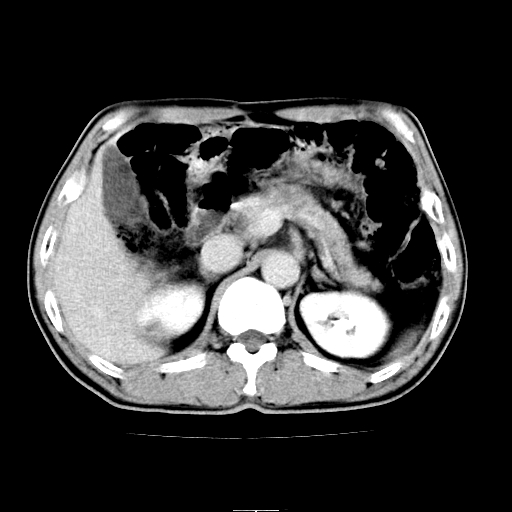

患者男,64岁,胃癌术后三个月,无明显不适。请讨论一下胰头前方小圆形低密度影为淋巴结还是肠管?

增强第6幅图上有气液平相通,是肠管,右肾低密度灶形态不规则似有壁结节,不除外转移.

应该考虑是肠管,理由1、平扫和增强对比,形态和内部的密度有明显改变。2、增强图片可见明显气液平面。

是肠管影,肠壁有强化。

一个形态变化大应该是肠管。

另一个上下观察不成形,强化也不符合淋巴结表现故考虑术后改变。

另外,胰腺体部密度在平扫和增强时均不太均匀,似有数个小的囊状低密度区存在。不知道增强时其他期如何?应该高度警惕为转移性病变。

胰头右侧低密度影卡考虑为肠管;胰头前部低密度影,增强环形强化,结合临床首先考虑转移灶,其次考虑淋巴结结核(中心干酪性坏死)。